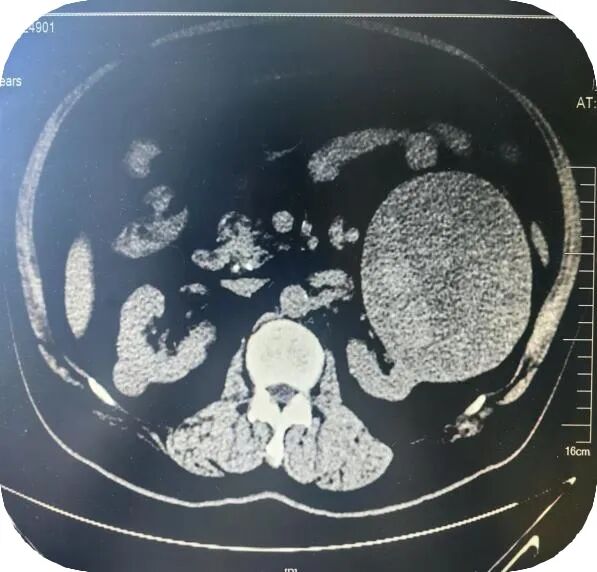

近日,贵州航天医院泌尿外科团队成功为一名患者实施了全腹腔镜下巨大肾癌根治术,这不仅标志着泌尿外科团队医疗技术的一次重大突破,更为患者在家门口带来了治疗的希望。 案例分享 67岁的王先生因“体检发现左肾包块1年”,发现时未予重视及治疗,但近期发现腹部包块增大就前往我院泌尿外科门诊就诊。患者入院后检查发现肌酐轻度升高,泌尿系增强CT及MRI均强烈提示左肾存在恶性肿瘤性病变,包块大小约200×150×120mm,且右侧骼骨高密度影提示需排除骨转移可能。 在与患者及家属沟通后,他们坚持手术治疗,泌尿外科主任石英、副主任医师李凯多次组织相关医生进行术前讨论和评估,精准设计手术方案,在泌尿外科团队奋战2小时后,成功为患者实施全腹腔镜下巨大肾癌根治术,切除巨大肾脏肿瘤。术后病理确诊为肾细胞癌,左侧肾上腺皮质有增生伴多发小结节,周围组织未见癌浸润。患者术后恢复良好,1周后便安全出院。 术 前 术 后 1 什么是肾癌 肾癌,全称为肾细胞癌,是指肾脏细胞发生癌变,异常地生长、增殖并向其他全身器官侵袭、转移的一种恶性疾病。它是原发于肾细胞的一种癌症,有多种细胞类型,其中60%~85%为透明细胞癌,主要源于肾小管上皮细胞。肾癌的瘤体多为实性,表现为类圆形肿块。 2 肾癌的症状 早期: 肾癌早期通常没有典型的症状,多数患者是在体检或做B超、CT检查时发现肾脏有占位性病变。 中晚期: 1.腰痛、腹部包块或肉眼血尿。 2.由于肾癌吸收大量的血红素和营养成分,导致肾脏促红素分泌下降,出现贫血现象。 3.少数肾癌病人会出现病理性转移,引起病理性骨折现象。 4.肾癌病人还可能出现泌乳现象。 5.由于肿瘤局部转移或局部扩散,肾癌病人还可能出现局部疼痛和肠梗阻症状,部分病人还会出现消瘦、恶液质现象。 6.当肾癌引起肾脏静脉瘤栓并导致下腔静脉梗阻时,还会出现下肢水肿症状。 3 全腹腔镜下巨大肾癌根治术如何治疗肾癌? 全腹腔镜下巨大肾癌根治术是一种比较先进的手术方式,它利用腹腔镜技术,通过微小切口在腹腔或后腹膜腔途径进行手术,完整切除整个肾脏及其周围可能受累的组织。 手术过程中,医生会在患者腹部做几个小切口,通过这些切口插入腹腔镜及其相关手术器械。腹腔镜具有高清摄像功能,能够将腹腔内的图像实时传输到显示器上,使医生能够清晰地看到手术部位。在腹腔镜的引导下,医生进行精确的手术操作,切除整个肾脏及其周围筋膜内的组织。 4 全腹腔镜下巨大肾癌根治术优势 与传统的开放手术相比,全腹腔镜下巨大肾癌根治术具有以下优点: 创伤小:手术切口小,减少了组织损伤和出血量。 恢复快:术后患者疼痛轻,恢复速度快,缩短了住院时间。 并发症少:由于手术操作精确,减少了术后并发症的发生。 美观性好:手术切口小且隐蔽,有利于保持患者的美观性。 注:图片来源于网络,如有侵权,请联系删除。 推荐 阅读 1.【航医精品】泌尿外科精品技术介绍——经尿道钬激光前列腺剜除术(HoLEP) 贵州航天医院泌尿外科 专家团队 石 英 泌尿外科主 任 学科带头人 主任医师 中国医师协会泌尿外科分会感染协作组委员,奥林巴斯泌尿系软镜西南区专家组成员,西南地区第一批输尿管软镜专家组成员,贵州省医学会泌尿外科分会委员,贵州省性学会理事,贵州省性学会常务委员,贵州省泌尿外科专业医疗质量控制中心专家委员会委员。 从事泌尿外科专业近30年,熟练掌握泌尿系各类疾病的诊治,具有丰富的临床经验,擅长泌尿系结石、腹膜后肿瘤及泌尿系肿瘤的手术治疗,对泌尿系感染、泌尿系结核、尿源性脓毒血症的救治有独到的见解及抢救经验,在贵州省率先引入输尿管软镜技术,同时在男科领域,对男性阳痿、早泄及前列腺疾病有很深的研究。 李 凯 泌 尿 外 科 副 主 任 医 师 贵州航天医院肿瘤腔镜组带头人,擅长肾癌根治术、输尿管癌根治术、膀胱及前列腺癌根治术、腹腔镜输尿管狭窄切除吻合术、输尿管切开取石术等手术,在遵义市率先开展泌尿系结核后膀胱挛缩全腹腔镜下膀胱扩大术。 贵州省医学会泌尿外科分会青年委员,遵义市医学会男科分会常务委员,遵义市医学会泌尿外科分会常务委员。 李国成 泌 尿 外 科 副 主 任 医 师 中国人体健康科技促进会男科学专业委员会委员,贵州省性学会泌尿外科分会委员,贵州省医学会男科学分会委员,遵义市医学会男科学分会副主任委员兼秘书长,遵义市医学会泌尿外科分会常务委员,贵州航天医院男科带头人。 从事泌尿外科及男科工作10余年,曾多次在上海交通大学附属第一人民医院,中国中医科学院西苑医院进修学习男科;擅长性功能障碍的诊治,男性整形手术,前列腺增生激光手术,显微手术等。 贵州航天医院泌尿外科简介 • ✦ 基本情况 ✦ • 贵州航天医院泌尿外科是贵州省临床重点专科,具备先进检查及治疗设施,可进行各种泌尿外科所需临床检查和治疗。拥有先进的美国科医人钬激光碎石及前列腺剜除系统、体外冲击波碎石机、等离子电切设备、奥林巴斯输尿管软镜、STORZ输尿管电子软镜、腹腔镜、膀胱镜、输尿管镜、肾镜、美国KLS能量平台及各种显示系统,男科专用的ED超声治疗仪、精液分析、显微镜、男科检查平台、尿动力仪、结石分析仪等。 除了传统的开放性手术外,已常规开展各种微创性手术,同时在尿动力学及结石成分方面的研究已走在省内前列,在贵州省内率先开展前列腺钬激光剜除术治疗前列腺增生症,等离子电切术在前列腺增生、膀胱肿瘤、在尿道狭窄中手术的应用,腹腔镜手术(肾囊肿、肾上腺肿瘤、肾输尿管结石及肾切除手术),肾癌、肾盂癌、输尿管癌、膀胱癌、前列腺癌根治术,泌尿系统畸形及泌尿系重建,在遵义地区率先开展钬激光技术应用于泌尿外科临床,率先使用输尿管硬镜、软镜及肾镜联合钬激光治疗泌尿系结石,开展尿动力学、泌尿系结石分析,填补了遵义地区空白,率先开展针状肾镜激光碎石取石术。 • ✦ 诊疗范围 ✦ • 一、泌尿系肿瘤、炎症、小儿泌尿系疾病、男科疾病、女性排尿异常与盆底功能障碍疾病。如:肾上腺肿瘤、肾肿瘤、肾盂输尿管肿瘤、膀胱肿瘤、前列腺肿瘤、生殖器肿瘤、排尿功能障碍、泌尿系畸形及肾后性肾功能障碍、女性尿道综合征、泌尿系感染以及泌尿道疼痛、婴幼儿男性性腺和性器官发育异常、青春期男性性器官和功能发育延迟、男性生殖功能障碍、男子节育与避孕、中老年男子生殖健康以及老年男子性腺功能减退症、生殖器官常见疾病、男性生殖器感染以及性传播疾病、外生殖器官畸形与矫形、损伤。 二、泌尿系结石。如:肾结石、输尿管结石、膀胱结石、前列腺尿道结石、泌尿系畸形合并结石、尿流改道术后合并泌尿系结石。 三、独立开展男科疾病诊治,设有单独男科门诊。 • ✦ 咨询信息 ✦ • 门 诊 地 址:门诊部110诊室 坐诊时间: 周一至周五(08:00-12:00;13:00-17:00) 周末及节假日(08:00-12:00;13:00-16:00) 咨询电话 门 诊:28690349 医生办公室:27677326 病房护士站:27677518 END